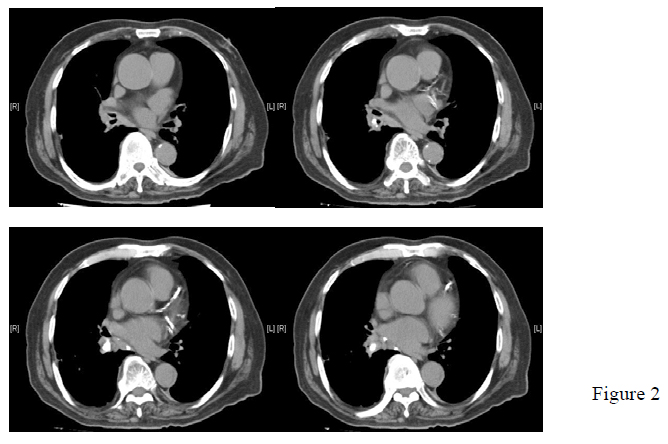

Further work-up included a contrast CT thorax, which showed right lower lobe consolidation and a calcified lesion in his right lower bronchus (Figure 2).